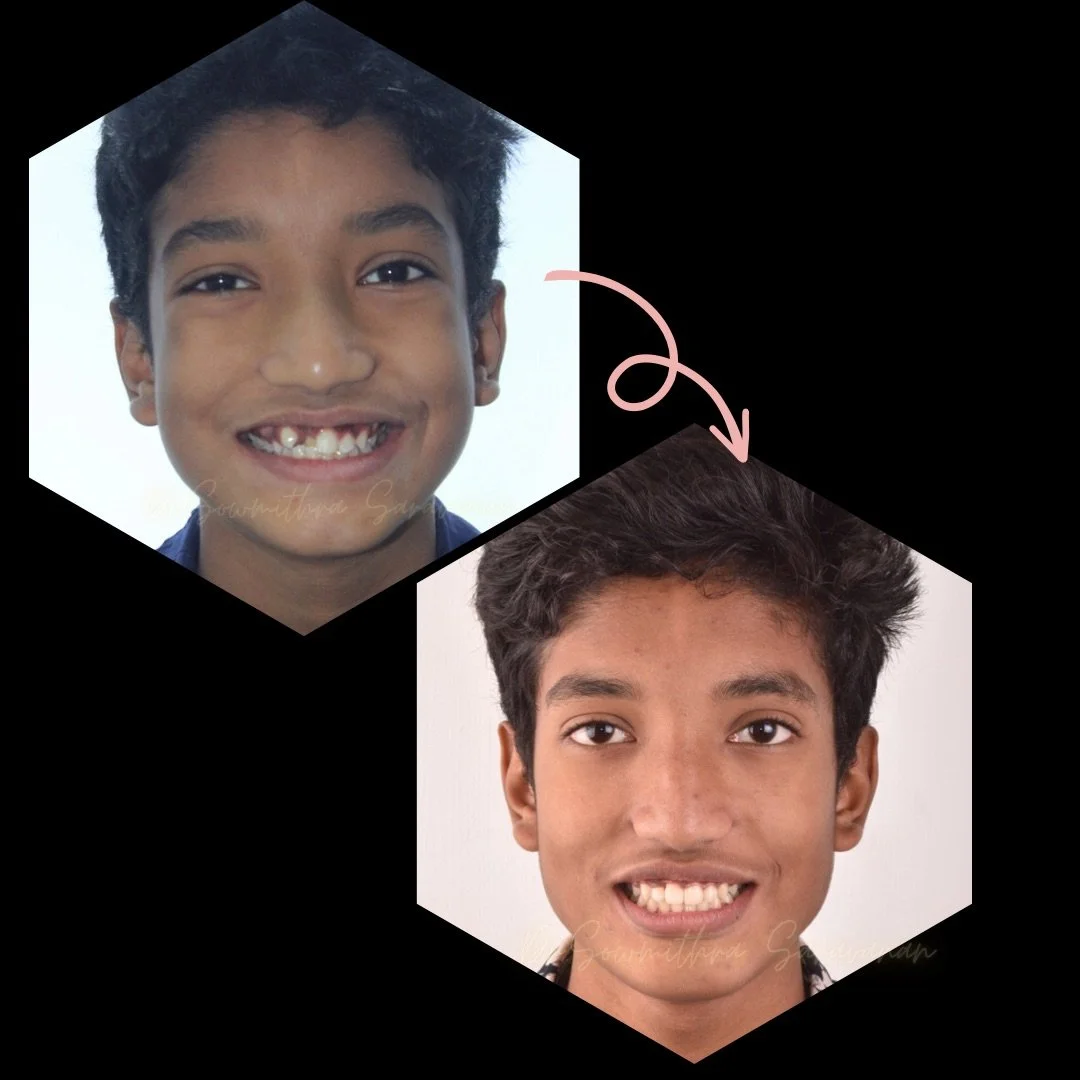

SMILE CORRECTION FOR ADOLESCENTS

SMILE CORRECTION FOR ADOLESCENTS